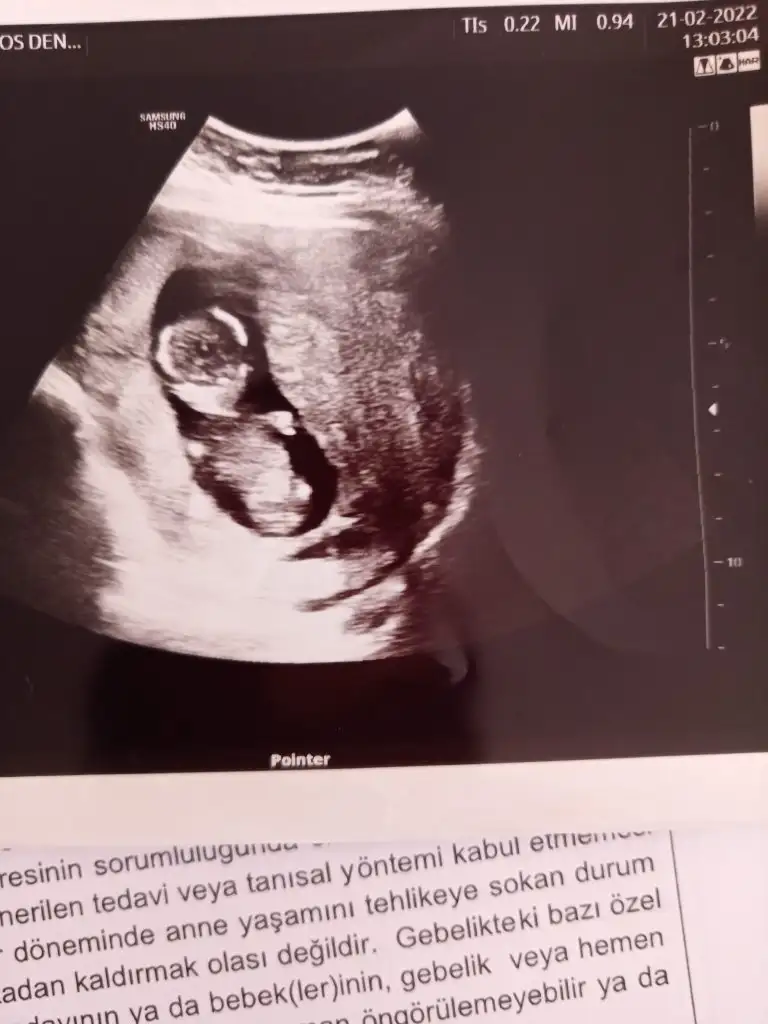

Ben çıktım şükürler olsun tam 12 haftalikmis folik asiti kesti doktor.d vitamini damla,demir ilaci ferrum, bide decavit vitamin başladı.ayrica akıntım olduğu için flora duzenleyici bir probiyotik aldirdi..ikili testin kararini tamamen bana birakti ben de kabul etmedim ikili testi yaptirmayacagm Allahtan gelen her şeye raziyim dedim.ve bir ay sonraya kadar simdilik boyle